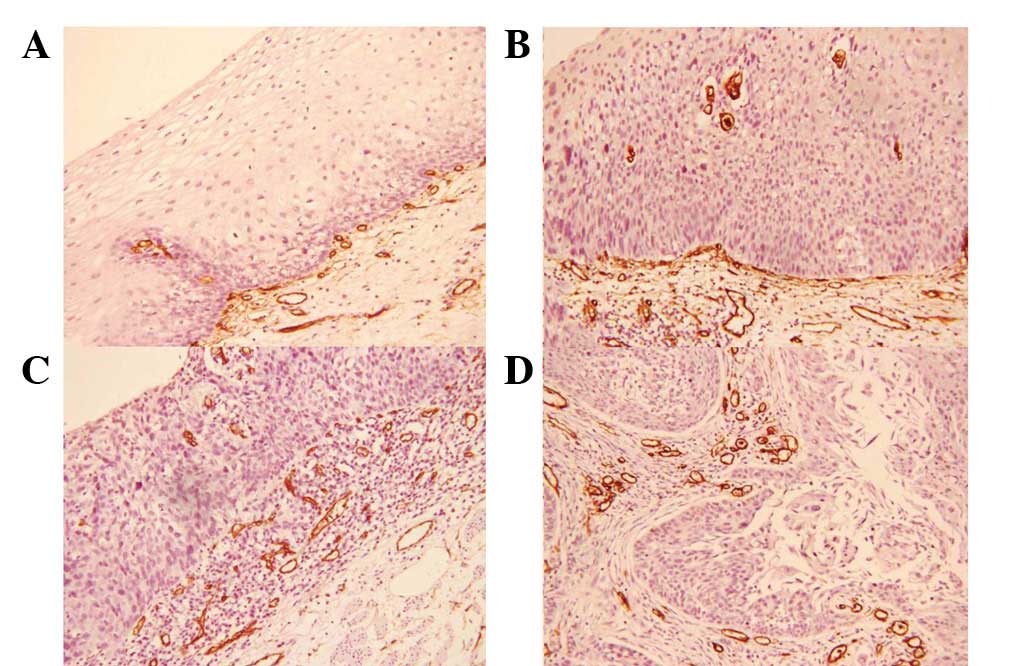

Hypertonicity esophageal anal sphincter

Gastroenterological Disorders

Colorectal Surgery